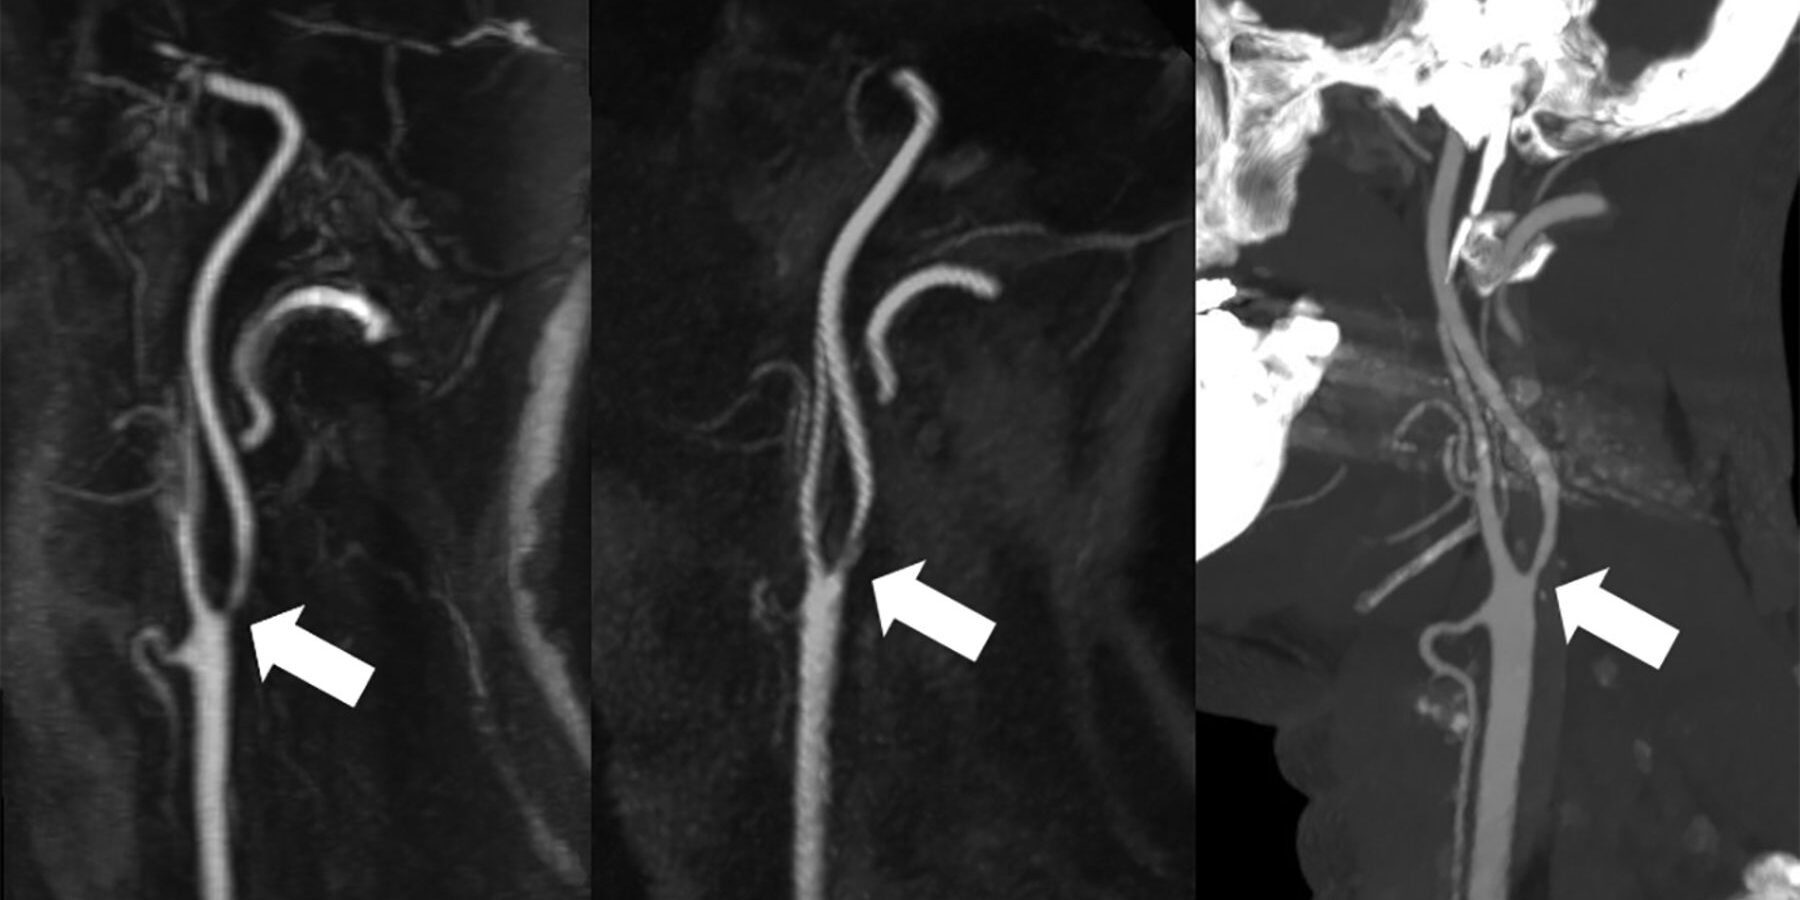

(IMMAGINE IN ALTO) Non-Contrast-Enhanced Carotid MRA: Clinical Evaluation of a Novel Ungated Radial Quiescent-Interval Slice-Selective MRA at 1.5T S. Peters, M. Huhndorf, U. Jensen-Kondering, N. Larsen, I. Koktzoglou, R.R. Edelman, J. Graessner, M. Both, O. Jansen, M. Salehi Ravesh American Journal of Neuroradiology Sep 2019, 40 (9) 1529-1537; DOI: 10.3174/ajnr.A6171

L’immagine in alto mostra una comparativa tra una CE-MRA con mezzo di contrasto (a sinistra), una QISS senza mezzo di contrasto, e uno studio TC (a destra).

QISS che sta per quiescent-interval slice-selective , ormai disponibile da alcuni anni, è stata utilizzata prevalentemente per il circolo periferico (primi studi dal 2010) , in alternativa alle tecniche TOF (che soffrivano di troppi artefatti misti) e alle tecniche FBI Fresh Blood Imaging che richiedevano complicate regolazioni di trigger cardiaco e che a causa delle stenosi fornivano spesso risultati variabili.

Nell’immagine iniziale in alto sui tronchi sovraaortici si è evitato il trigger cardiaco utilizzando una lettura radiale del k-spazio, per l’effettiva riduzione degli artefatti da movimento e pulsazione.